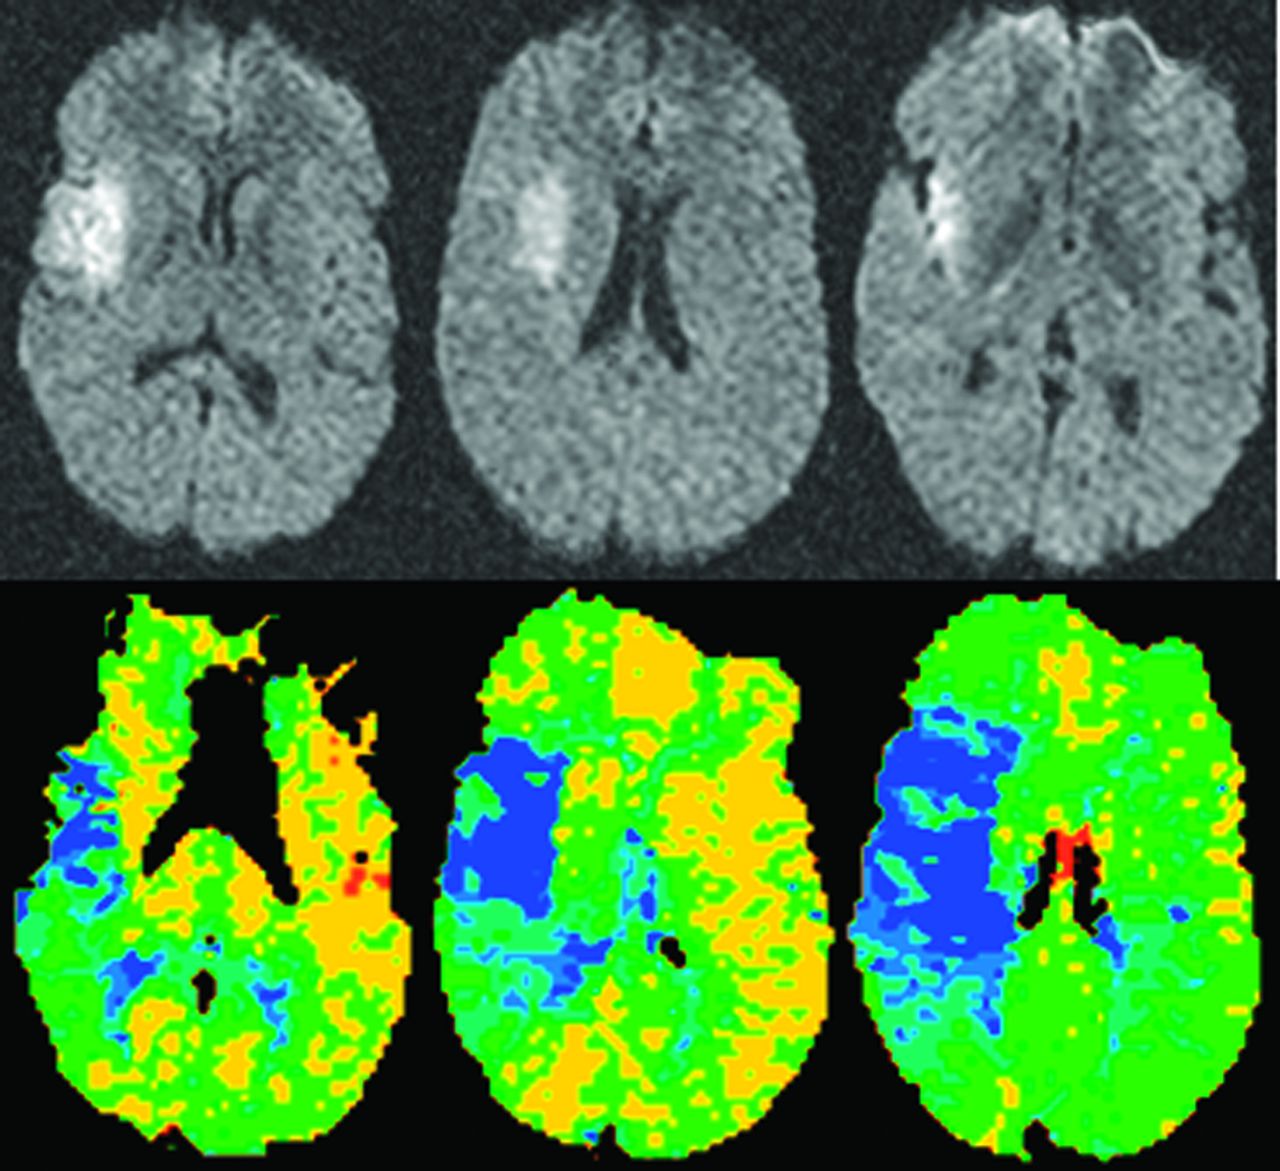

灌注CT是第二个成像模式被用来确定一个近似的半影急性缺血性中风患者。灌注CT图像上获得超快的CT扫描仪通过快速重复扫描后注入碘化对比材料。与一个信号冲刷bolus-contrast灌注CT扫描生成的曲线,可以生成cb v半定量的cb v和地图都未都未。26cb v随着缺血变得更严重,崩溃,都未与灌注CT缺血性核心被确定为一个地区与cb v明显下降。都未CBF和MTT地图展示缺血灌注值低于一个阈值定义为异常的地区的大脑区域。缺血半影操作上定义为该地区的CBF cb v或MTT异常值高于都未崩溃的阈值(图2)。27,28使用灌注CT是目前受到几个因素,与DWI-PWI相比。这些因素是有限的报道缺血性脑(只有2 - 4片对于大多数扫描仪,尽管整个大脑覆盖率现在可以在更新模型),更可靠地确定阈值识别CBF cb v / MTT和异常,都未和小动物成像技术建模工作。灌注CT的一个主要优点是更广泛的可用性和访问与MRI相比。样本大小适度的做的一项研究证明类似目标的识别病人的治疗决定3 -见到时间窗与灌注CT与DWI-PWI相比,但这一发现需要确认更多的患者在多个网站。29日当一些与灌注CT解决当前的问题和可比性DWI-PWI界限不明的近似被证实,实际问题表明,它将成为最常用的成像工具界限不明的近似。